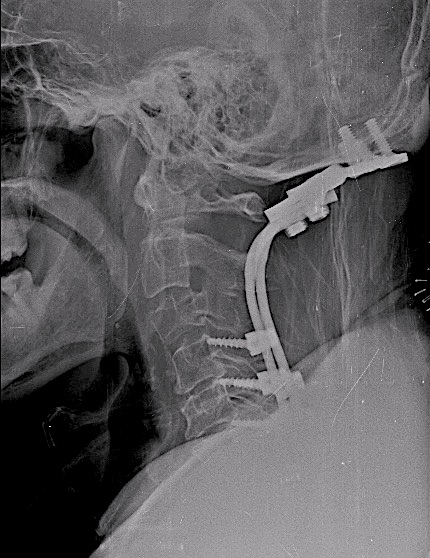

La resonancia postoperatoria demostró una adecuada descompresión. El paciente fue derivado para tto oncológico de rescate. La evolución postoperatoria fue favorable desde el punto de vista neurológico, con recuperación progresiva de la focalidad hasta autonomía completa.

Control 1 año